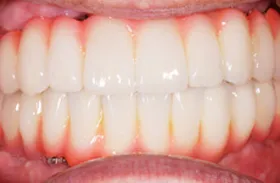

咀嚼障害のため来院されたケース(all-on-4)

60代 男性

咀嚼障害、歯茎の痛みを訴えられ、来院されました。

■治療前

■治療後

| 主訴 | かみにくい・全体的に歯茎が腫れて痛みがある 痛みがある |

|---|---|

| 治療方法 | 上下顎に複数本のインプラントを使用し、一体型の補綴物をセット |

| 治療期間 | 約1年 |

| 通院回数等 | 約20回 |

| 費用 | 約600万円 |

| リスク・副作用 | 補綴物が過度な力で破損するリスクがある |